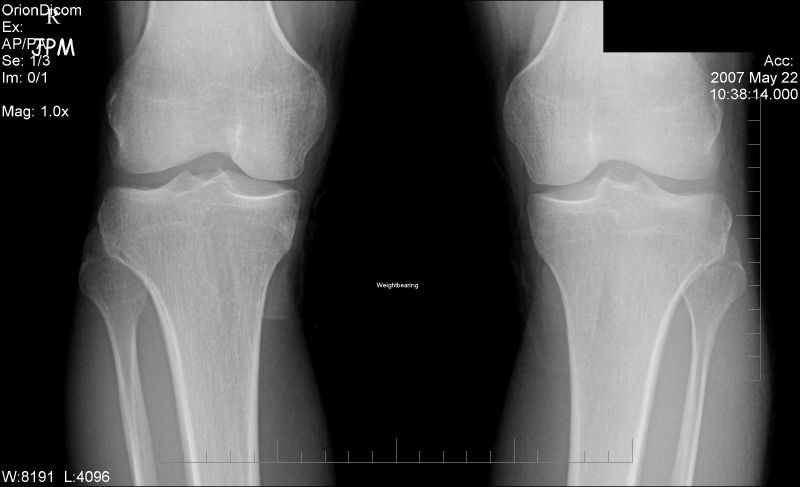

Właśnie tam, u lekarza ortopedy okazało się, że uraz jest znacznie poważniejszy niż sądzono. Na  wykonanym natychmiast badaniu RTG stawu kolanowego uwidoczniło się uszkodzenie kompleksu tylno-bocznego (PLC) lewego kolana. Rezonans magnetyczny potwierdził uraz i fakt, że doszło  także do wieloodłamowego złamania w kości piszczelowej.

Zarzucono postawienie błędnej diagnozy, co skutkowało pogorszeniem stanu zdrowia pana J. oraz opóźnieniem prawidłowego procesu leczenia. W szczególności wskazano, że lekarz chirurg  na SORze nie zlecił  badania RTG stawu kolanowego oraz nie skonsultował przypadku z lekarzem ortopedą. Postępowanie lekarza, niezgodne z aktualną wiedzą medyczną spowodowało, że nie wdrożono leczenia przewidzianego dla leczenia złamania kości piszczelowej.